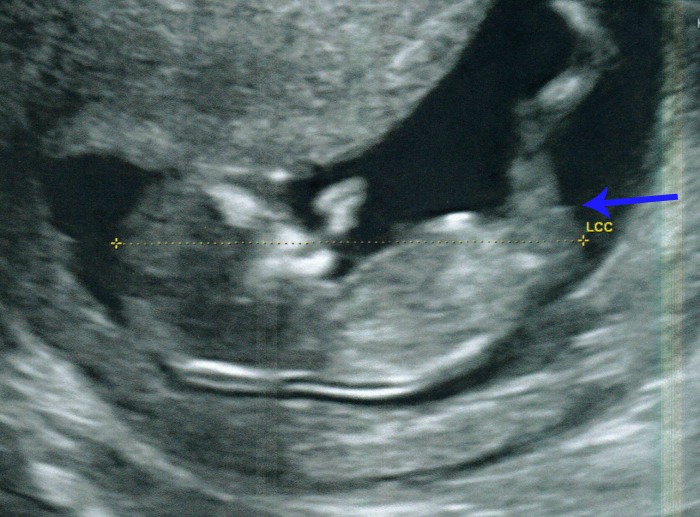

Please guess away ladies - I have put an arrow where I personally think you can see a nub peeping out just based on what I remember from the scan video.

Attachment 21173